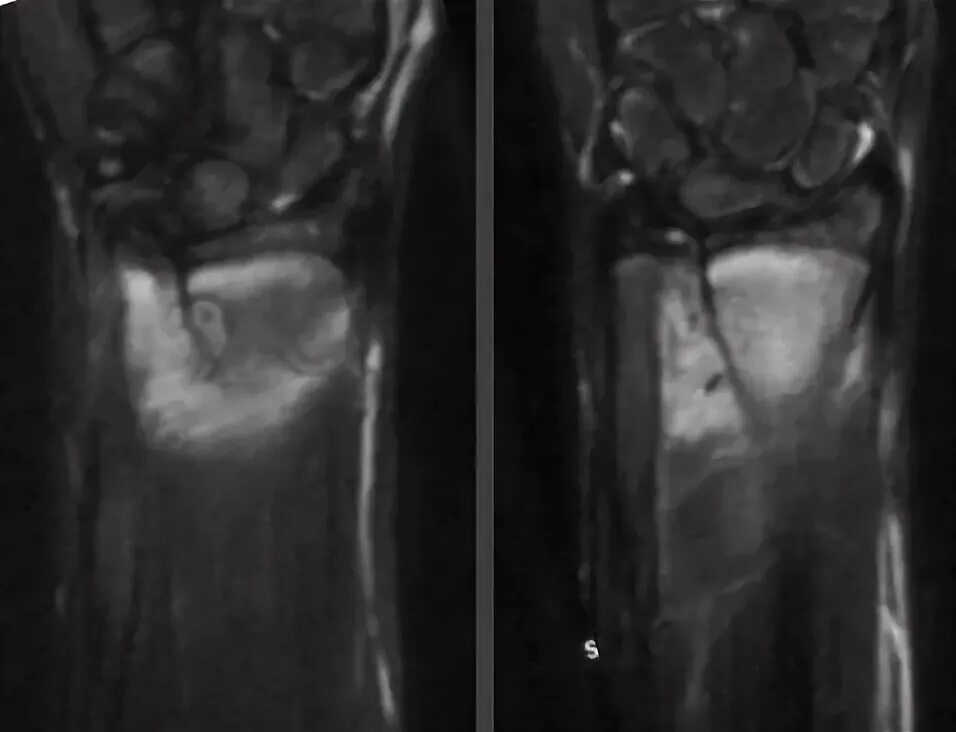

Остеома мрт